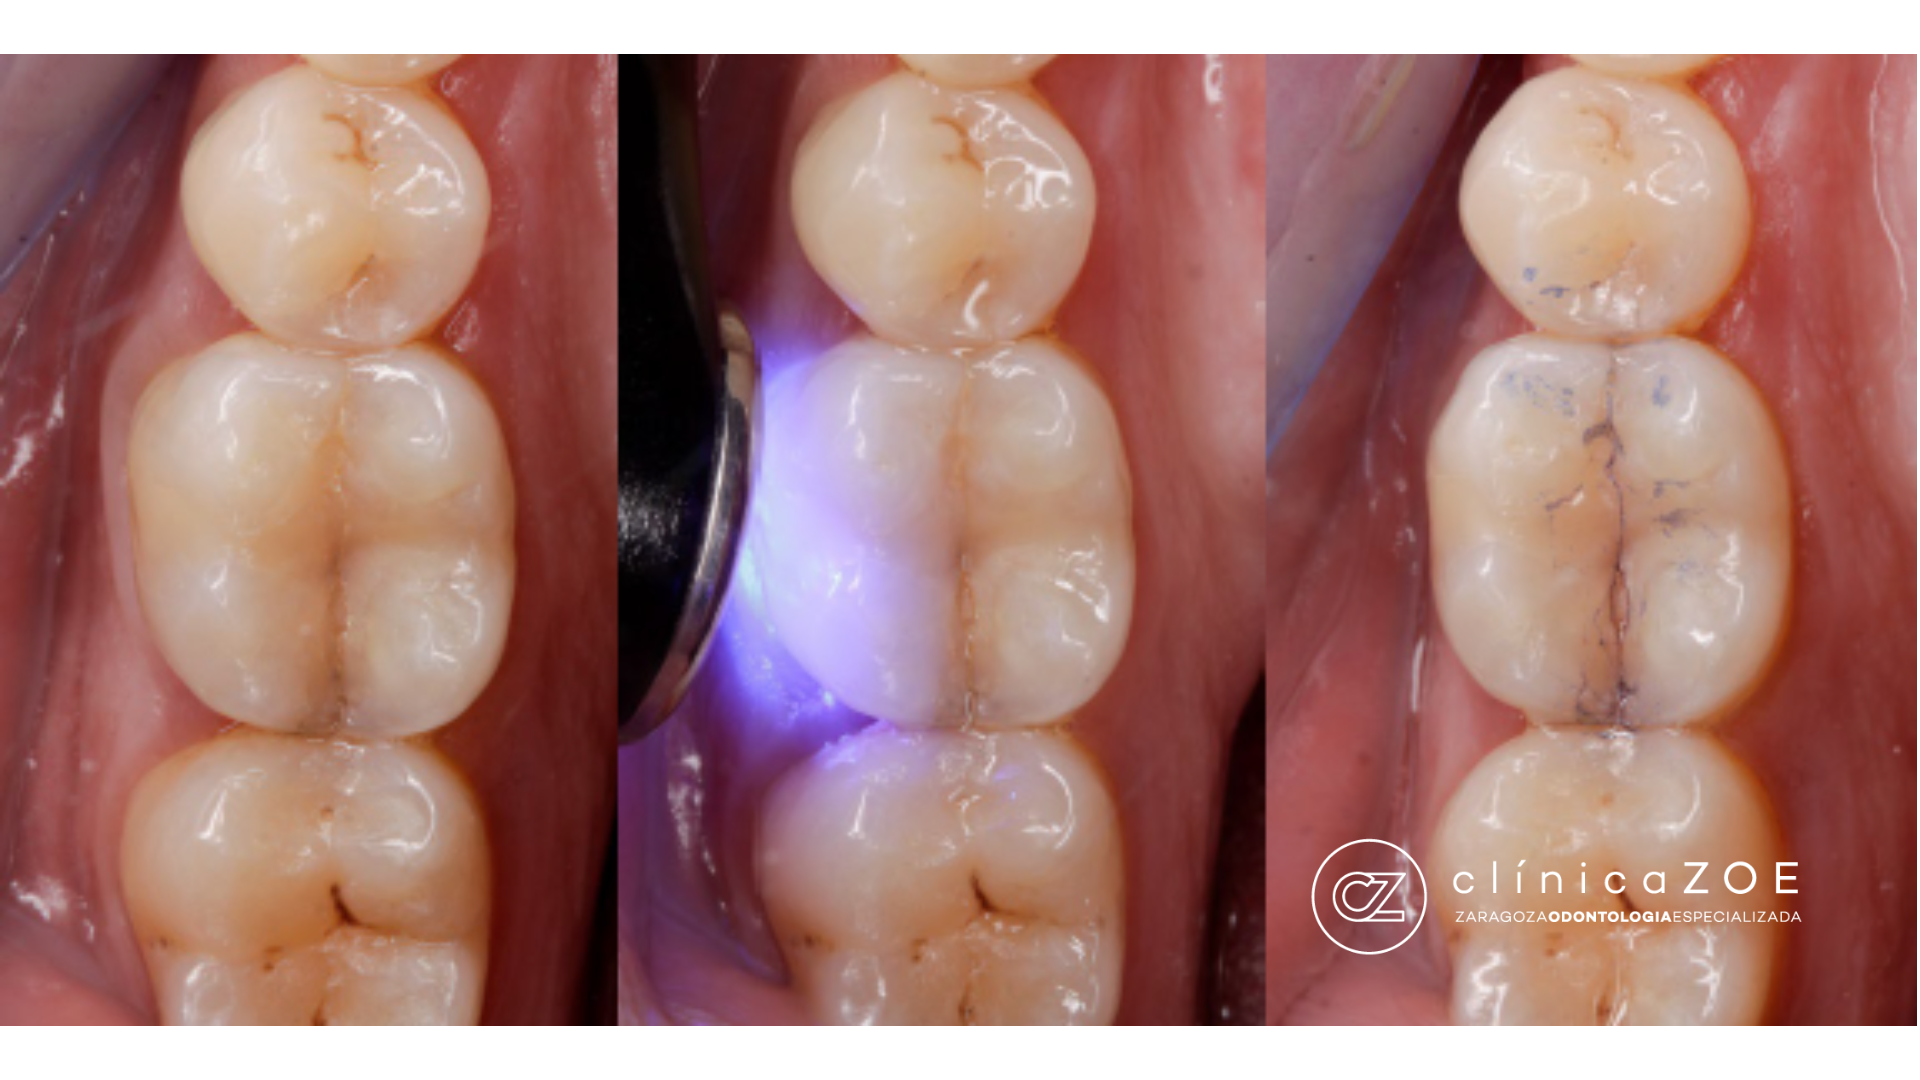

3. Magnificación con microscopio: permite ver microgrietas invisibles, aplicar tinciones y valorar su trayecto.

2. Exploración dirigida con pruebas funcionales: utilizamos tests de mordida selectiva y sondaje periodontal para detectar surcos estrechos y profundos.

Cuando la fisura es superficial o limitada, y la pulpa está viva y asintomática, sellamos con materiales adhesivos y protegemos cúspides con incrustación (onlay) o corona parcial.